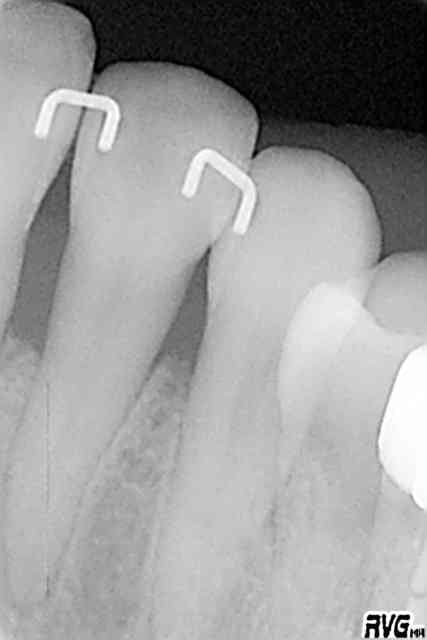

Les attelles d'Abjean j'en pose chaque semaine (ou presque), l'avantage ENOOOOORME par rapport à un "jonc noyé" c'est la rétention 3D que tu n'as pas avec le jonc!

et le délabrement est bcp moindre, en plus quand une attelle lache tu la changes, et pas tout le bastringue!

1) les forêts drill: tu as quelle réf. ???

2) le fil c'est du jonc en 0,8 mm

3) tu fais une gorge horizontale reliant les 2 points de contact jusqu'à la dentine (prof 1 mm) fraise HL 008

4) un léger avant trou à la fraise boule 008 aux extrémités de la gorge (komet H 009)

5) forage basse vitesse prof 1 à 2 mm les puits doivent être le plus parallèle possible (dans le tiers proximal de la dent à distance raisonnable de la pulpe ;-)

6) confection de l'attelle grâce à une pince à bec plat fine modifiée qui te permet de faire toutes les tailles d'entre-axe

7) essayage et puis souvent réessayage et scellement ou collage si tu en as.

C'est comme cela que Le Pr José Abjean nous l'a appris...à la fac.

C'est joli, mais je trouve que sur les radio, les trous sont plus prodonds que la contention et je trouve cela invasif vs fil ou contention classique. Pour quelques cas bien précis, ok, mais pas trop fréquente l'indication non ?

Ben si en fait, c'est la seule:

1 a être discontinue (donc refaisable sans tt déposer encore une fois)

2 a avoir une rétention axiale, vestibulo palatine, et disto mésiale (3 axes)

3 assez facile à mettre en oeuvre (par rapport à la manipulation d'un long fil que tu colles d'un bout qu'il faut tenir pour ne pas qu'il bouge :(....

4 délabrement moins important et risque de fracture de la dent bcp moindre (bord incisal par exemple)

5 résultat immédiat esthétique et absence d'interférences occlusales car entièrement incluse dans les puits et sillons réalisés.